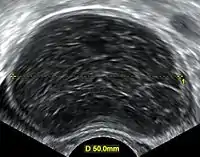

Transvaginal ultrasonography of a hemorrhagic ovarian cyst, probably originating from a corpus luteum cyst. The coagulating blood gives the content a cobweb-like appearance.

Ovarian cysts are usually diagnosed by ultrasound, CT scan, or MRI, and correlated with clinical presentation and endocrinologic tests as appropriate.[10]

Ultrasound

Follow-up imaging in women of reproductive age for incidentally discovered simple cysts on ultrasound is not needed until 5 cm, as these are usually normal ovarian follicles. Simple cysts 5 to 7 cm in premenopausal females should be followed yearly. Simple cysts larger than 7 cm require further imaging with MRI or surgical assessment. Because they are large, they cannot be reliably assessed by ultrasound alone; it can be difficult to see posterior wall soft tissue nodularity or thickened septation due to limited ultrasound beam penetrance at this size and depth. For the corpus luteum, a dominant ovulating follicle that typically appears as a cyst with circumferentially thickened walls and crenulated inner margins, follow up is not needed if the cyst is less than 3 cm in diameter. In postmenopausal patients, any simple cyst greater than 1 cm but less than 7 cm needs yearly follow-up, while those greater than 7 cm need MRI or surgical evaluation, similar to reproductive age females.[11]